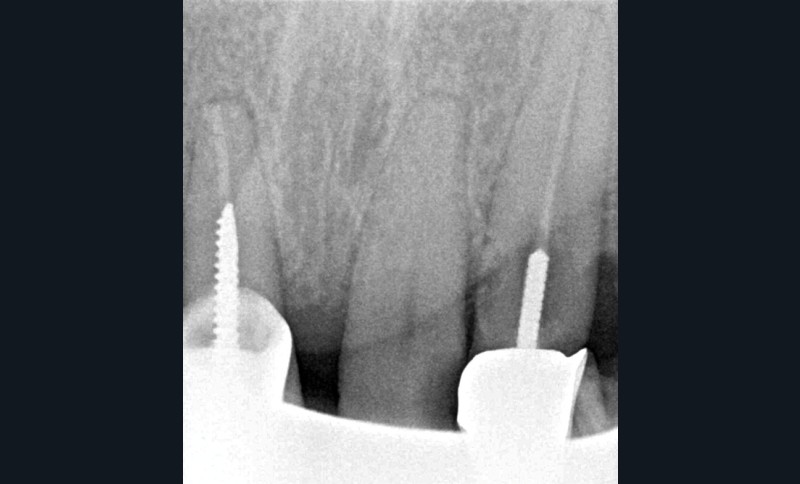

Un patient de 84 ans, en bon état de santé générale, consulte pour la perte de trois couronnes solidarisées métalliques 17, 16 et 15 qui permettaient la rétention d’une PAP à châssis métallique (fig. 1 à 5).

– 17, 16 sont à l’état de racines, 15 est déjà préparée et ne présente aucune symptomatologie pulpaire ;

– 13 est intacte ;

– 12 est couronnée et présente une mobilité importante et un épaississement ligamentaire ;

– 11 est couronnée ;